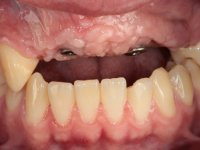

Male patient, 22 years old, non-smoker, appear in our dental office 6 months after a car accident where he lost teeth 21, 22, 23 and 24. Teeth 12 and 11 present mobility grade III, thus with a prognosis of extraction. The gengiva architecture of the edentulous area presents a recession and a flat surface.

TREATMENT NOTES:

The diagnostic wax-up enclose the possibility to include, or not, gum-shade ceramics to rehabilitate the interdental papillae. This two possibilities were presented to the patient due to the bone regeneration unpredictability (in our opinion), mainly vertically.

10 weeks after the surgery, a first impression was done to do a CAD-CAM provisional bridge (based on the diagnostic wax-up), that worked the soft tissue architecture during two months. This architecture was copied in a second impression by individualizing the impression copings in their emerging profile.